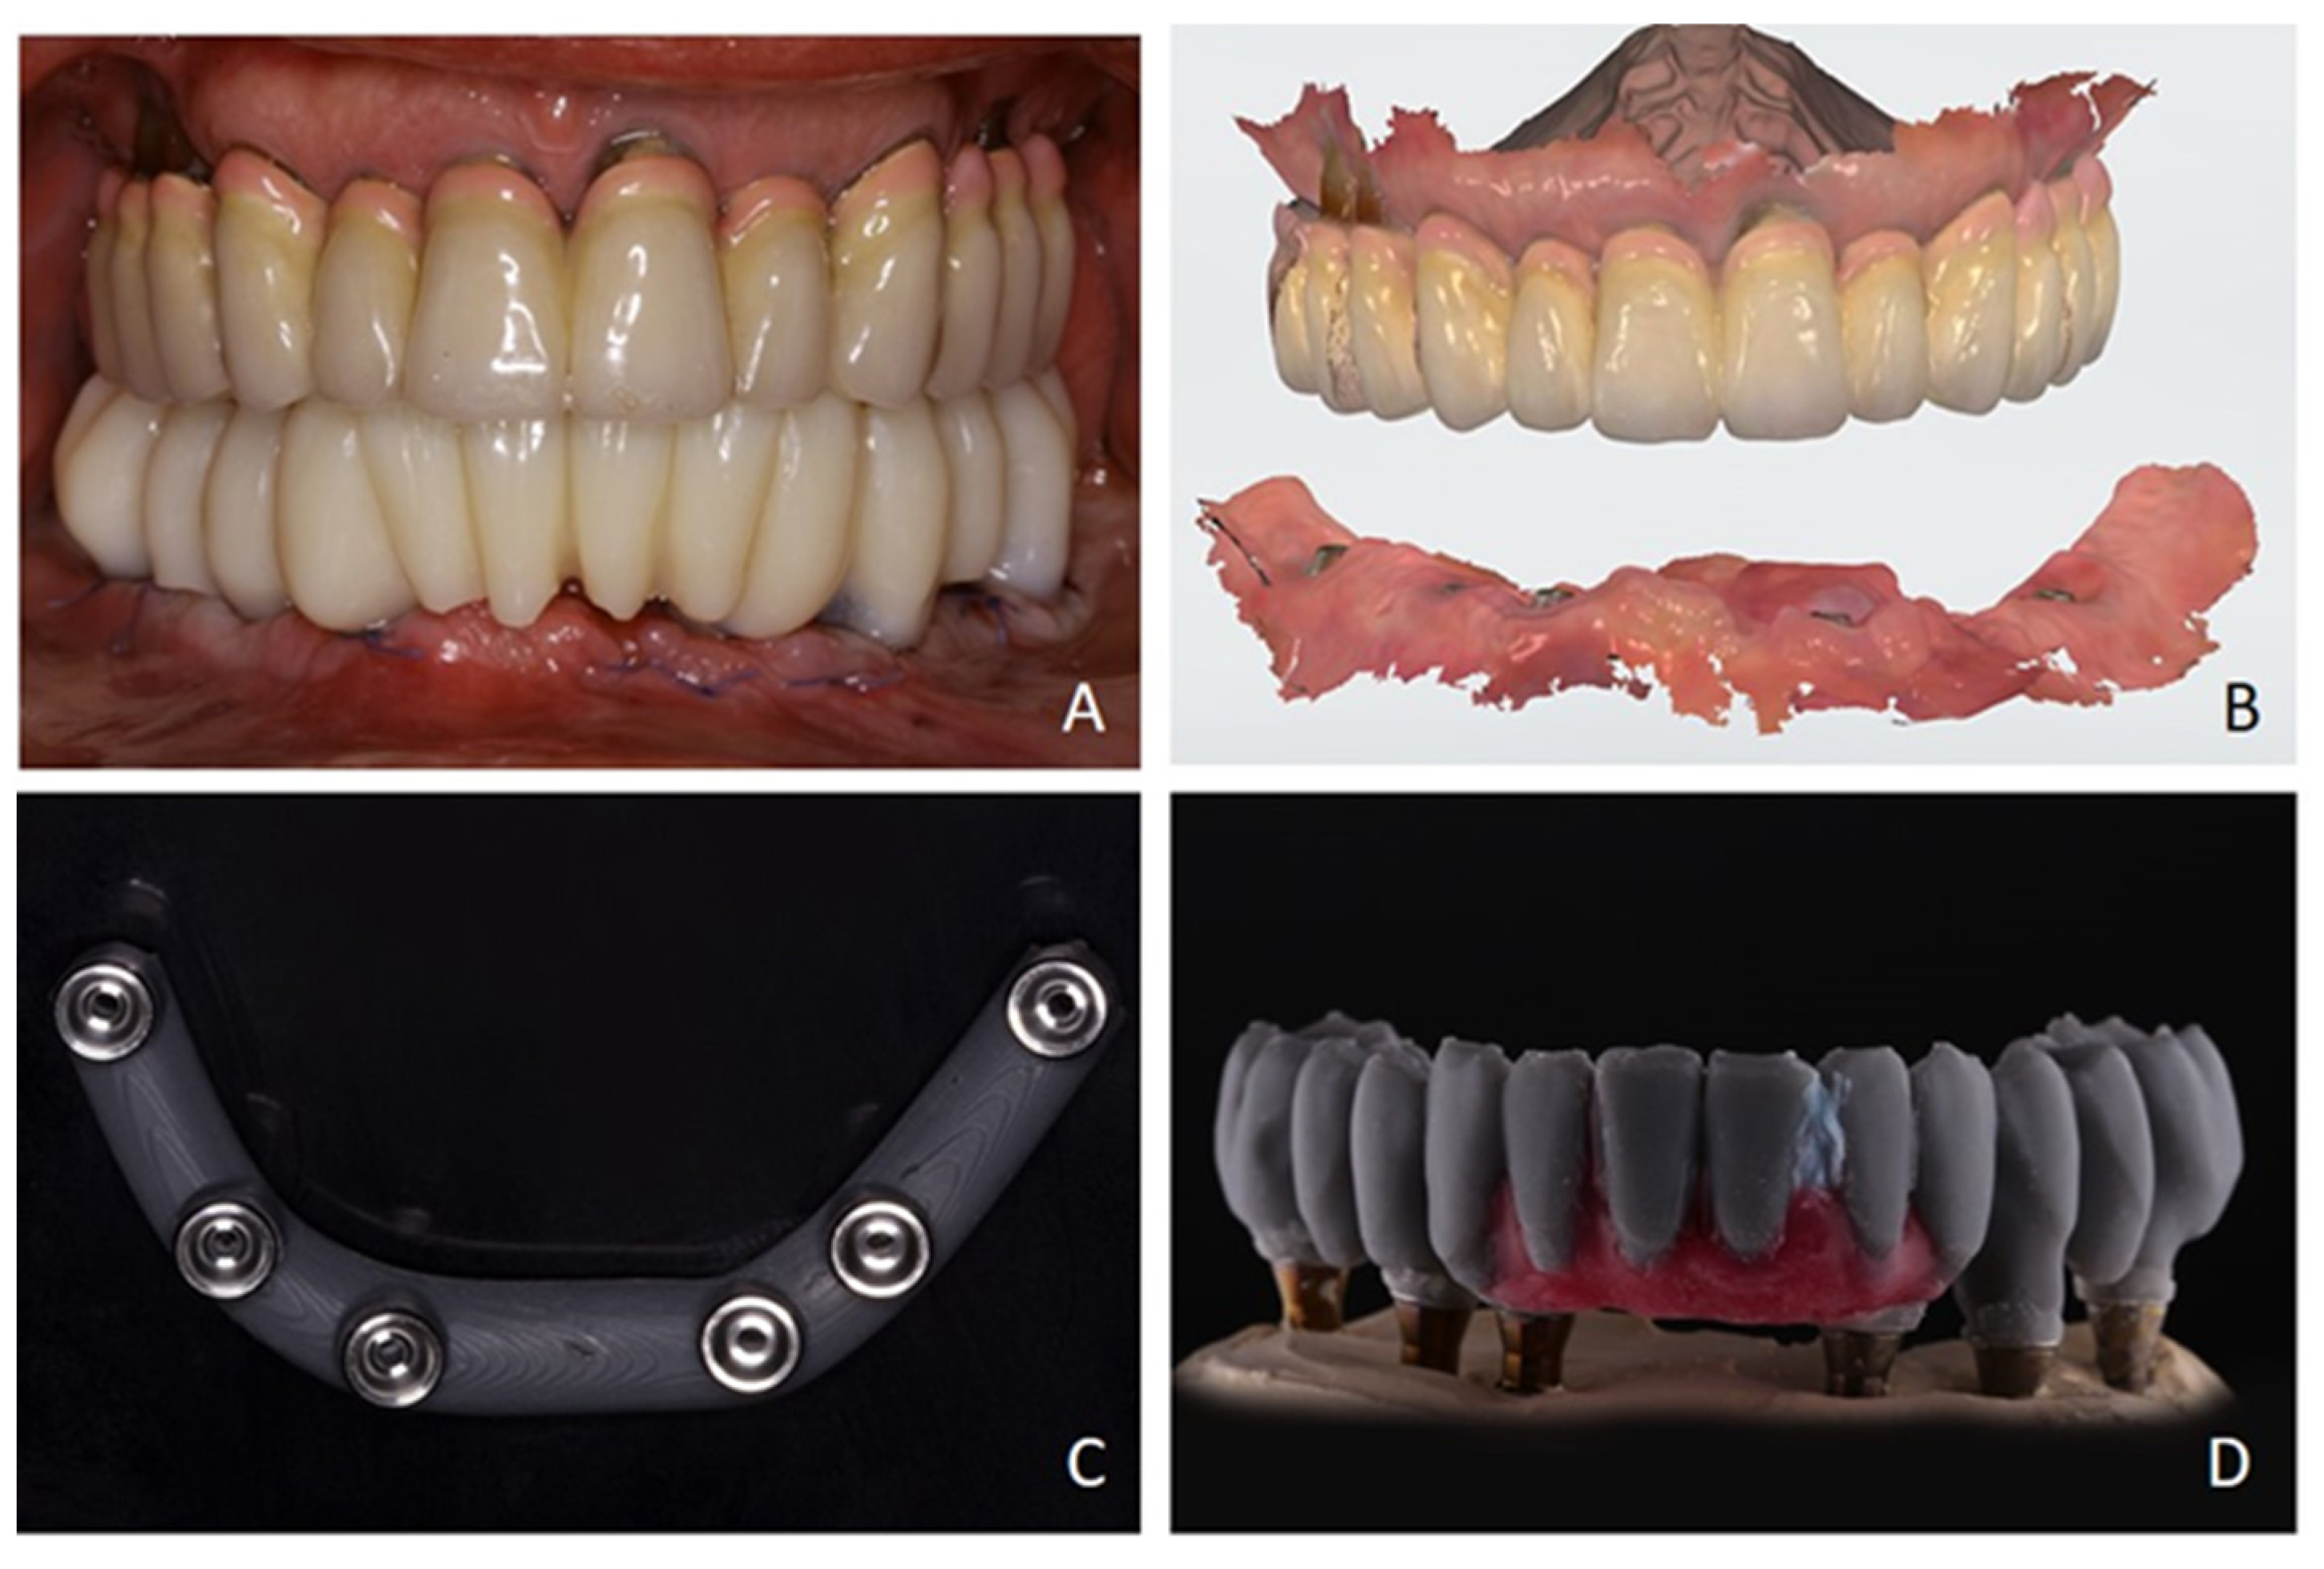

2. Case Report

3. Surgical Strategy

4. Discussion